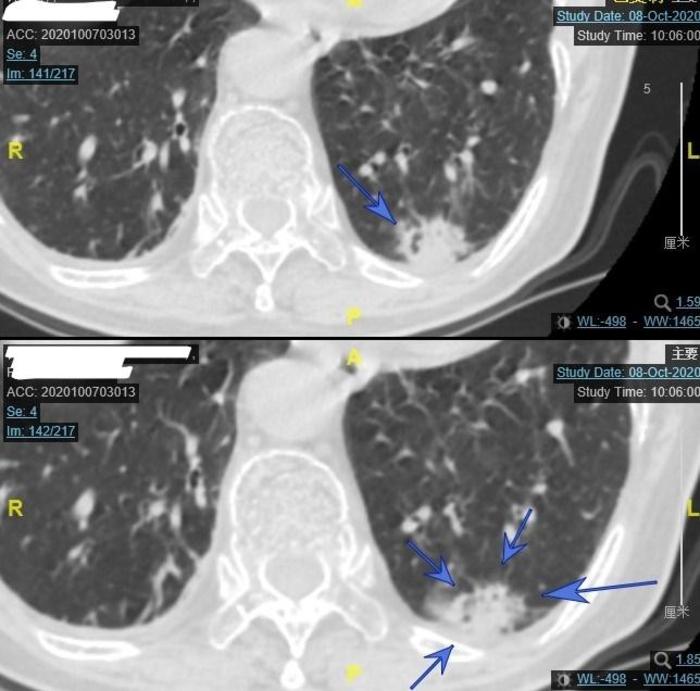

上图为今年9月份住院后的CT,由两张CT组成。上面的CT的蓝色 箭头指向的是混合磨玻璃结节内部有一个腰果形缝隙,所以这个结节不是一个纯实性结节。下面的CT上面两个蓝色 箭头和左下方蓝色箭头指向的是结节内部小空泡(看起来在白色背景中发暗一些)。右边的蓝色箭头指向的是结节外侧有一小块磨玻璃成分。

我对左下方混合磨玻璃结节外侧的一小块磨玻璃成分进行了CT值测量,发现其CT值是-165,因为其CT值是负的,不是正的,证实结节的外侧边缘有磨玻璃成分,所以这个结节一实性成分为主、磨玻璃成分为辅,是一个大型混合磨玻璃结节。即使不就行肺穿刺检查,也有95%的把握这个结节是恶性的肺癌,而且应该已经到了浸润性腺癌阶段。